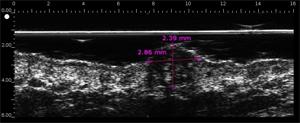

Melanomas Ecografía

Hipoecoica , con ecos de baja densidad. El eco de entrada no está muy marcado o ausente (ausencia de queratosis, ulceración) Melanoma ulcerado en el antebrazo (grosor medido a 3,68 mm en ecografía, grosor histológico). Lesión que infiltra la dermis. Melanoma en la oreja Carcinoma de células basalesCarcinoma de células basales en la frente (por encima de la arteria temporal)Carcinoma de células basales en la cara por encima del mastoidesCarcinomasuperficialCarcinoma pigmentado Nevo dérmico Lesión hipoecoica con muchos ecos, borde con la dermis adyacente mal definidoHistiocitofibroma  Lesión hipoecoica , pobremente limitada con muchos ecos.

• Melanoma superficial extenso, melanoma maligno; Índice de Breslow

DERMCUP promueve la eliminación del tumor con los márgenes apropiados

• Indica la extensión lateral y la profundidad de los cánceres de piel distintos del melanoma maligno (subclínico)

• Determina el índice de Breslow para el melanoma maligno